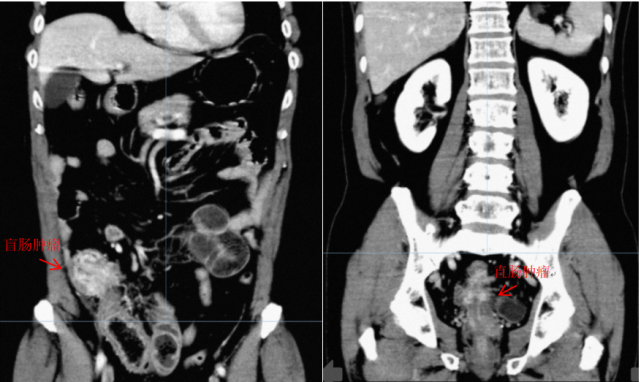

湖南长沙69岁的李先生2022年3月27日因腹部隐痛湖南省人民医院结直肠肛门外科门诊就诊,入院完善相关检查后诊断为“大肠多元癌并腹腔广泛转移并不完全性肠梗阻”。

在2022年4月3日施行的腹腔镜探查术中发现,大肠肿瘤分别位于盲肠及直肠中段,均广泛侵犯周围组织器官,且大网膜、腹膜多发种植转移,无法切除,遂予以末端回肠造口解除肠梗阻,并进行腹腔热灌注化疗。

经过9个周期的化疗及5个周期的靶向治疗后,评估盲肠及直肠肿瘤均有不同程度退缩。